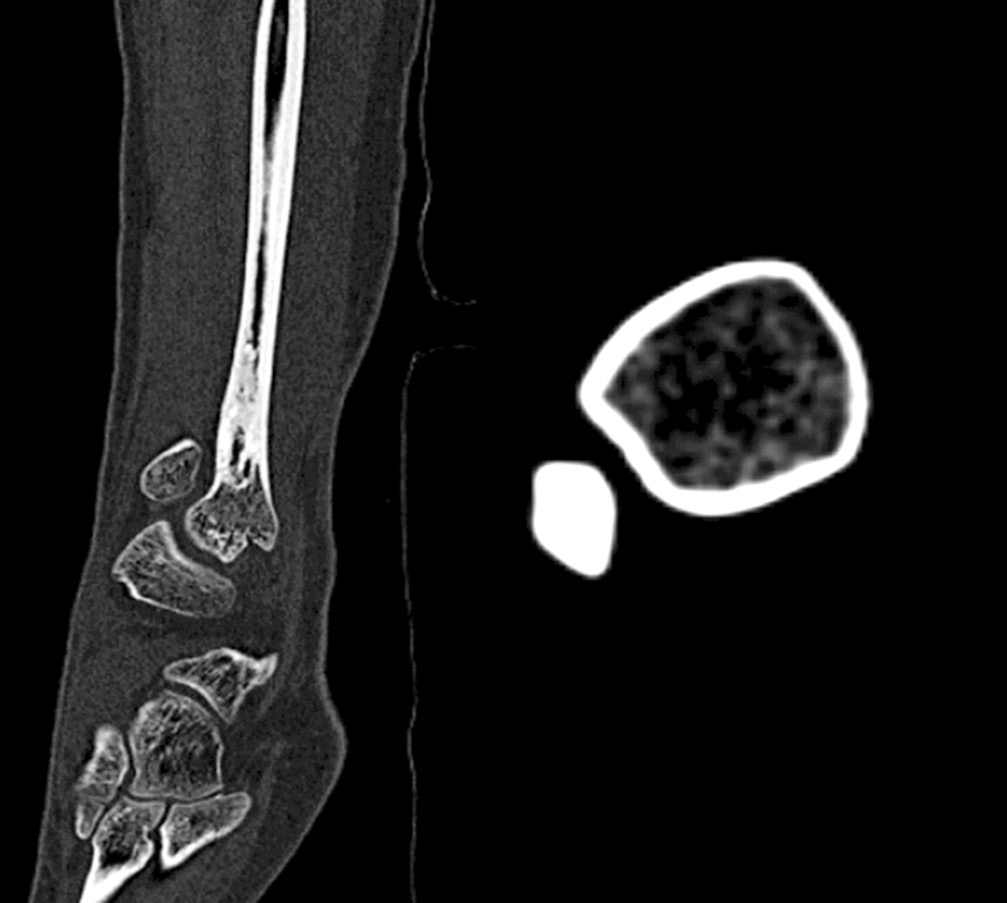

Ходьба при помощи костылей с дозированной нагрузкой на оперированную нижнюю конечность разрешена на 14-е сутки после оперативного вмешательства. На 21-е сутки после операции в зоне резекции костной кисты произошел перелом сохранившегося кортикального слоя малоберцовой кости без смещения (рис. 2). Иммобилизацию правой голени и стопы в постфрактурном периоде не осуществляли.

Рис. 2. Рентгенограмма. Состояние после оперативного лечения — краевой резекции пораженного отдела малоберцовой кости. Патологический перелом нижней трети малоберцовой кости, полость заполнена гранулами бета-трикальцийфосфата